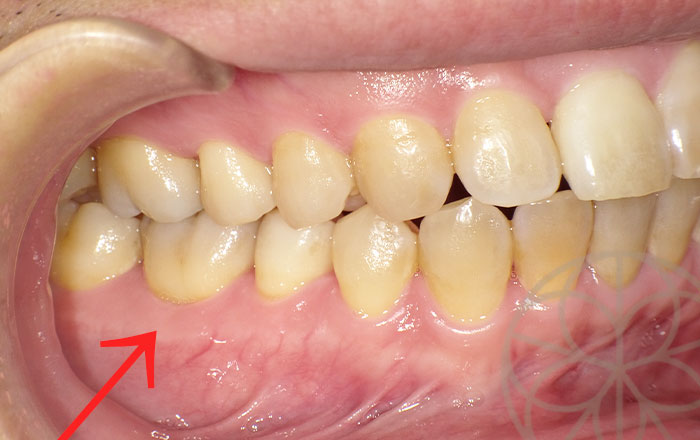

主訴 右下の歯に違和感があり気になる

治療前状況

感染根管治療

レントゲンを撮ると、右下の6番目の歯の根と根の間の骨(根分岐部の骨、赤矢印の部分)が消失しており、またこの歯の神経は壊死している状態でした。

この根分岐部の骨がかなり失われていることに関して、髄管と呼ばれる歯の内部から、根分岐部にかけて穴が開いている管があることが疑われました。

特殊なケースであるため、まずは根菅治療を行い、また根分岐部の失われた骨の状態を観察を行う治療方針としました。